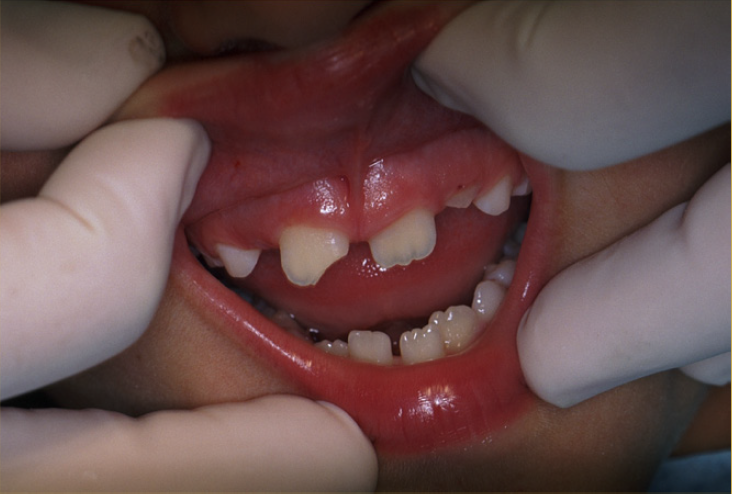

Fig 3. Images of Intrusion

Figure 3

Tooth Intrusion

Tooth intrusion occurs when the tooth has been driven into the alveolar process due to an axially directed impact (Figure 3). This is the most severe form of displacement injury. Athletes with intrusively luxated teeth should be immediately removed from play and transported to a sports emergency dentist.44

Pulpal necrosis occurs in 96% of intrusive displacements and is more likely to occur in teeth with fully formed roots. Immature root development will usually mean spontaneous re-eruption. Mature root development will require repositioning, surgery, and splinting or orthodontic extrusion. Treat relatively quickly since the pulp usually becomes necrotic - this can be treated with temporary filling of calcium hydroxide paste followed by root canal therapy.